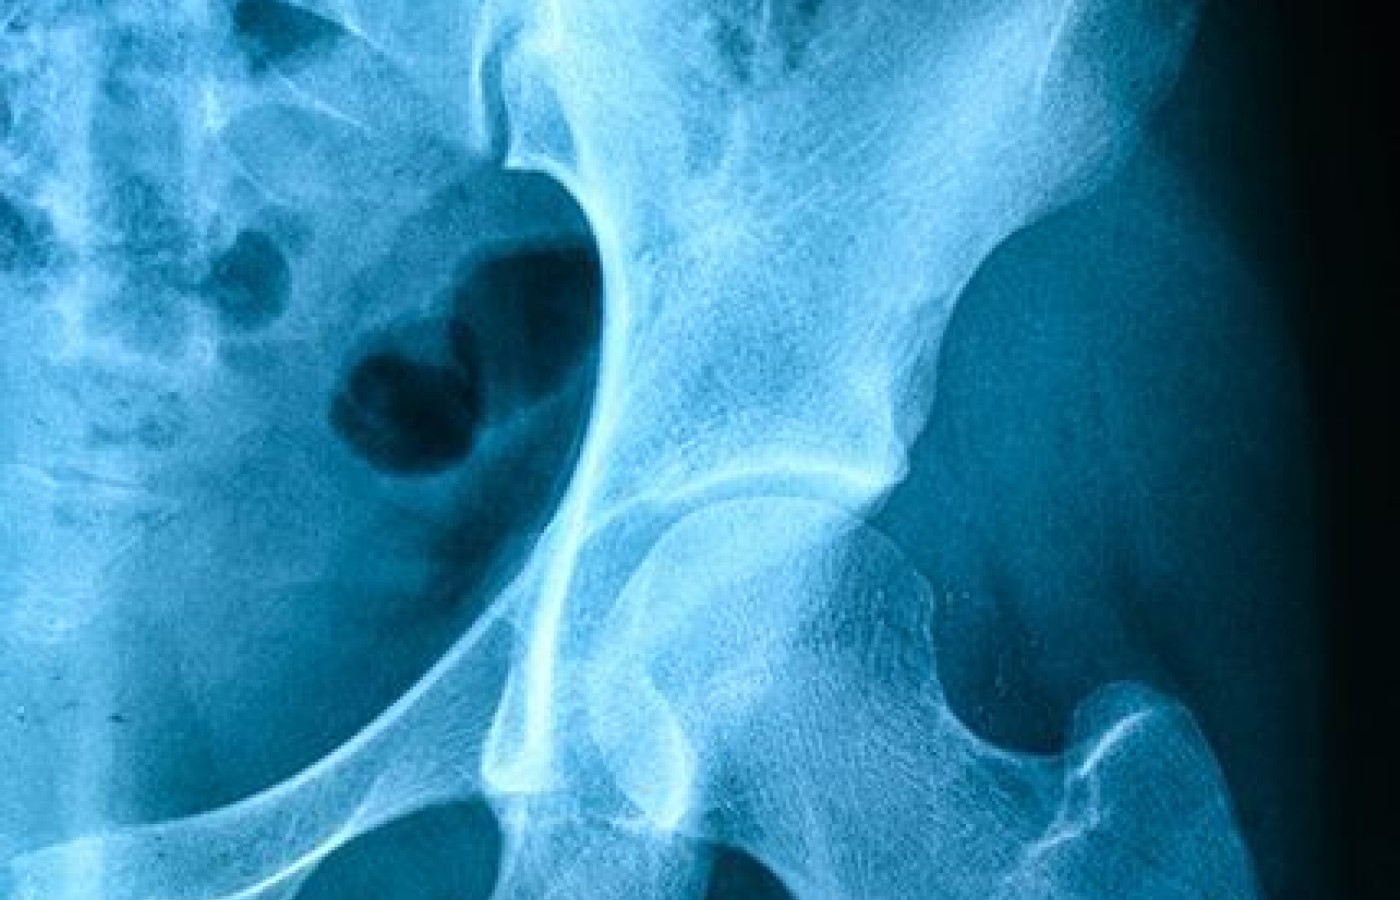

The strength of chiropractic physical rehabilitation is first and foremost CMT, closely followed by our appreciation of a whole-body approach to balancing the entire kinetic chain. Thoughtful rehabilitation of the low back goes beyond handing a patient a sheet of exercises, regardless of whether it is based on McGill's approach of neutral spine or the flexion model of Williams, Hodge or Cox. (These were all discussed in the first three articles in this series.) Now, it is time to look at the relationship of the hip (acetabular joint) and pelvis (sacrum and ilium) in low back syndromes.

My first three articles all addressed stability of the lumbar spine; however, restoration of proper joint motion in the hips and pelvis is equally essential for lumbar spine rehabilitation. This is often a missing link in low back rehab: failure to restore motion to the hips and pelvis. In addition, often the restoration of normal soft-tissue compliance to the LPH region allows the "adjustment to hold." Myofibrosis, trigger points, fascial restrictions, muscular weakness and tendinopathy all contribute to altered joint mechanics.

Assessment and treatment of the hips and SIJ in all planes of motion is beyond the scope of this article. The SIJ is complex in its biomechanics, having an upper and lower component with the sacral base being able to rotate both anteriorly and posteriorly on the ilium – nutation and counternutation, respectively.

Dynamically, in the gait cycle the ilium rotates around a frontal horizontal axis on the non-weight-bearing side, while on the weight-bearing side the ilium rotates around a vertical axis. Repetitive load, trauma, degenerative changes or maladaptive compensatory gait patterns can result in sacroiliac dysfunction. In addition, acquired hyper- or hypomobility of the SIJ results in altered load transmission, which further impacts the lumbar spine.

O'Boyle's contends the hip is a stability region; therefore, it tends to require extra attention to maintain mobility. Joint play of the hip in flexion, extension, long-axis extension, and internal and external rotation all need to be evaluated. Assessment of the LPH soft tissues for flexibility, strength, and tone via examination and functional movement screens completes the diagnostic algorithm.